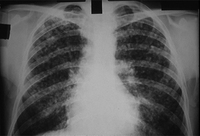

CXR of progressive massive fibrosis due to silica or coal exposure

From the personal collection of Kenneth D. Rosenman, Michigan State University